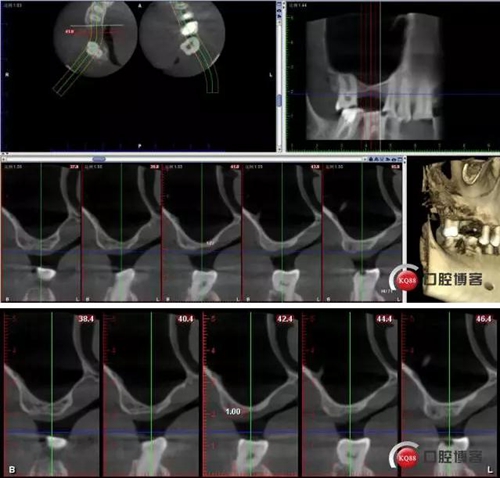

CBCT檢查:

術(shù)后CBCT

術(shù)前術(shù)后CBCT對比: